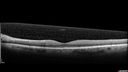

Chronic Endophthalmitis and Cystoid Macular Edema436 viewsVA 20/50 - Culture negative. Cleared with intravitreal antibiotics and decadron00000

Chronic Endophthalmitis and Cystoid Macular Edema390 viewsVA 20/50 - Culture negative. Cleared with intravitreal antibiotics and decadron00000

Chronic Endophthalmitis and Cystoid Macular Edema414 viewsVA 20/50 - Culture negative. Cleared with intravitreal antibiotics and decadron00000

Chronic Endophthalmitis and Cystoid Macular Edema402 viewsVA 20/50 - Culture negative. Cleared with intravitreal antibiotics and decadron00000